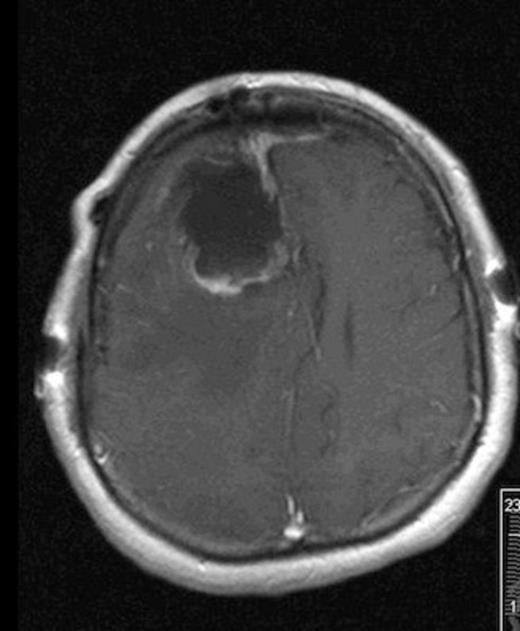

Post-operative MRI showing gross-total resection with some residual blood in cavity

She was taken to the operating the following morning for a bicoronal craniotomy for a gross-total tumor resection with neuronavigation (Fig 2). Pathology was a dural-based WHO Grade 1 supratentorial haemangioblastoma. Microscopic findings demonstrated large vessels and abundant capillary networks, with a cellular proliferation of large stromal cells with clear vacuolated cytoplasm (Fig 3,4,5). There were significant hyperchromatic nuclei and multiple areas of PAS positive pinkish globules (Fig 3,4,5).